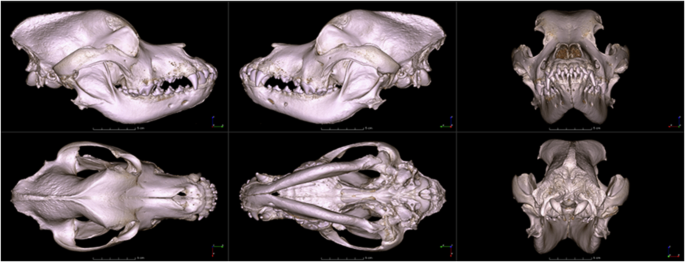

Volume cropping and viewport save

To generate an overview of the image volumes (without the necessity to download them for inspection of suitability), a further post-processing step was carried out. Volumes were cropped to remove extraneous surrounding regions (the space around the skulls), and screenshots were generated from six primary perspectives of the volume-rendered CT image series, resulting in left, right, front, back, top, and bottom views (Fig. 2). All of these images were created using 3D Slicer25, which can be found in the ‘Thumbnail images’ folder of the dataset.